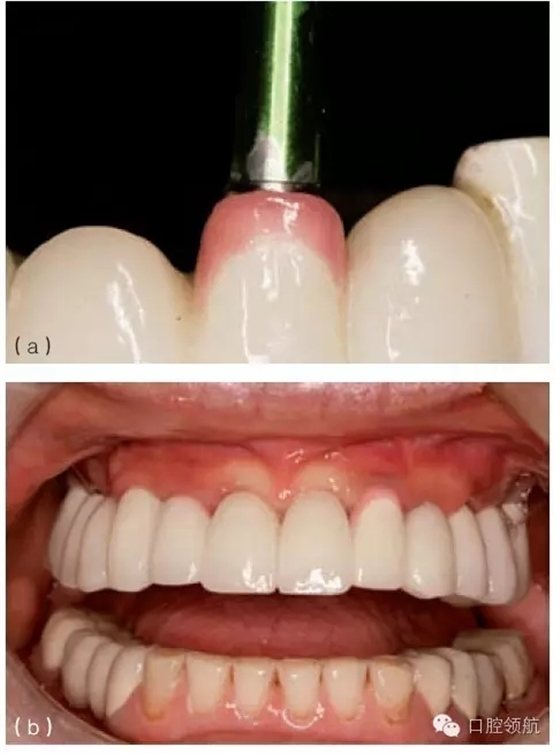

在種植體植入之前,有必要確定最終的修復(fù)方案,并且計算放置種植體修復(fù)部件所需要的空間。例如,對于單個粘結(jié)固位的種植修復(fù)體,從種植體平臺到對頜牙,最少需要7mm的空間。這個空間包括以下組成部分:基臺距對頜牙牙合面2mm;對粘結(jié)固位來說,即便聚合度非常平行的情況下,也至少需要4.5mm的預(yù)備高度,才能滿足固位要求;基臺與種植體交接的拋光肩領(lǐng)需要0.5mm。如果牙合間距離較小(如4.5~5mm),可以制作螺絲固位修復(fù)體(或UCLA的一體化冠)(圖9.23a,b)。實施種植手術(shù)時,必須考慮牙齦厚度及牙槽骨的水平。若有需要,可以施行牙槽嵴切除術(shù),以獲得額外的牙合間距離。另外,種植體可以高于、低于或平齊牙槽嵴頂,以便與未來的修復(fù)體匹配。但當(dāng)在修復(fù)期間考慮這些問題時,剩下的選擇就非常有限,只能在粘結(jié)固位或螺絲固位中選擇一種。有時,可以選磨對頜牙,來獲取少量的修復(fù)空間。另外,如果需要恢復(fù)垂直高度的話,可以通過升高咬合來獲得牙合間距離。

圖9.23 (a) 頰面觀, 牙合間距離不足(5mm)(相對于粘結(jié)固位),需要制作螺絲固位式修復(fù)體。(b)牙合 面和舌側(cè)觀,完成的螺絲固位式修復(fù)體。